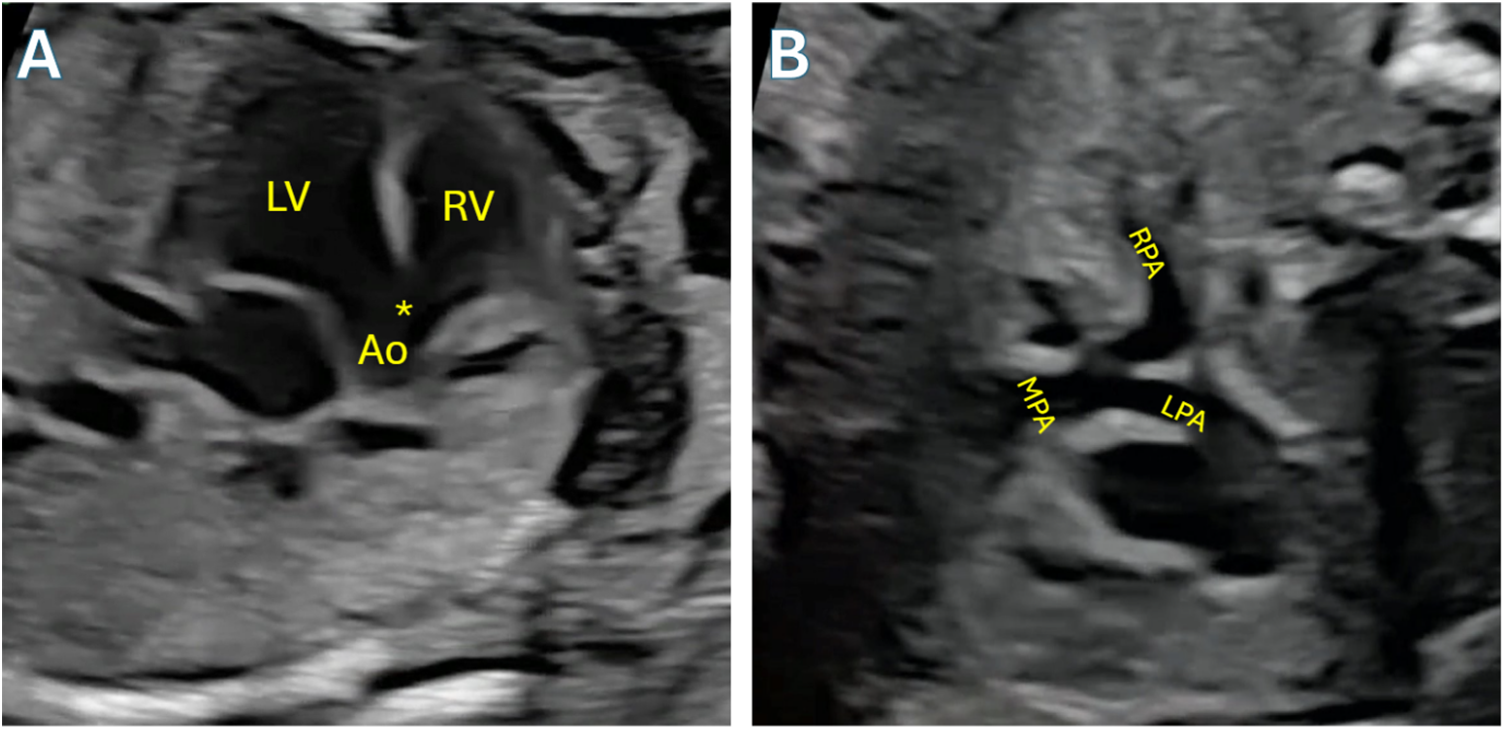

Figure 4: Fetal echocardiogram demonstrating Tetralogy of Fallot. A: Angling anteriorly from 4-chamber view to demonstrate the large VSD (asterisk) and overriding aorta (Ao). B: 3-vessel trachea view demonstrating size discrepancy between aorta and pulmonary artery, a hallmark feature of TOF, and confluent mildly hypoplastic branch pulmonary arteries. LV: Left ventricle; RV: Right ventricle; LPA: left pulmonary artery; RPA: Right pulmonary artery; MPA: Main pulmonary artery